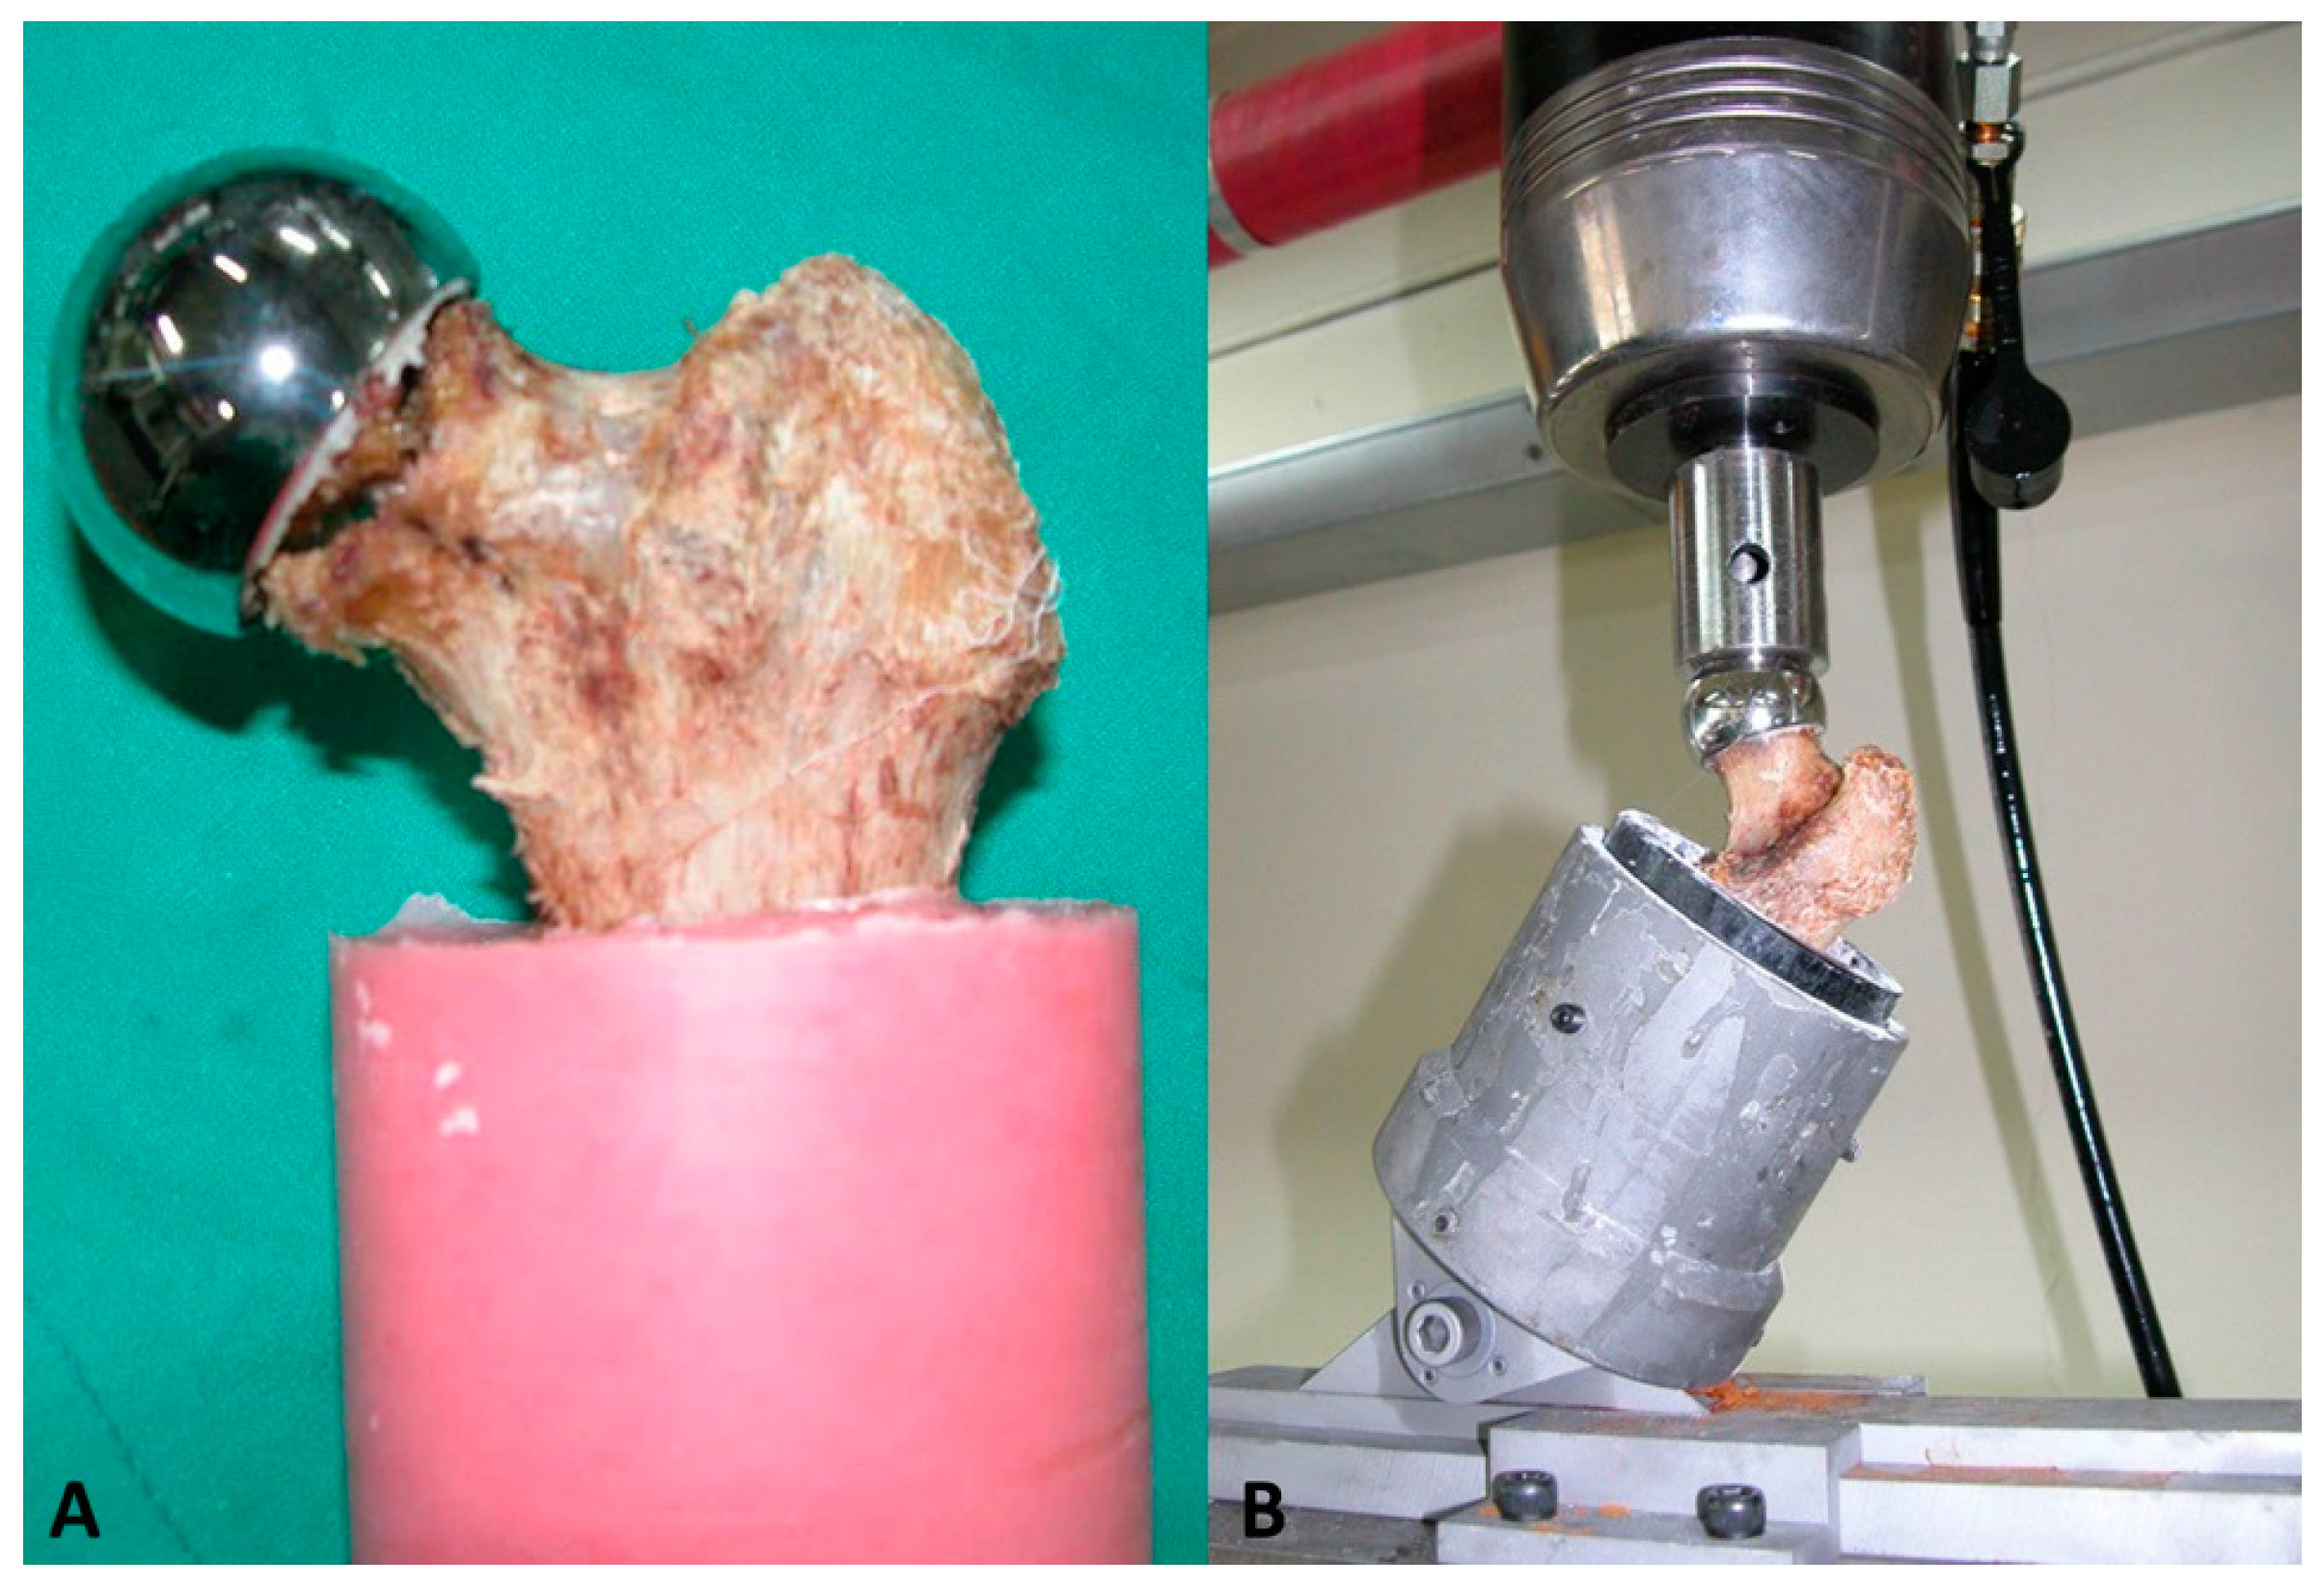

2.3. Assessment of the Biomechanical Stability of the Specimen